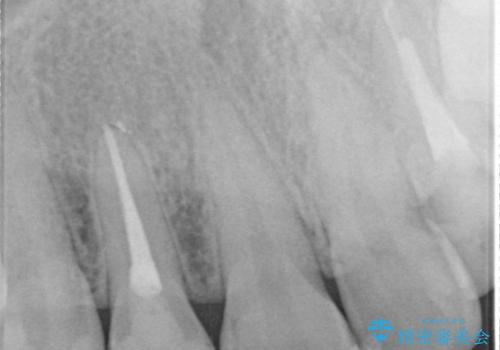

- 食べ物が歯間にはさまることを主訴に来院された患者様です。レントゲンより上顎両側切歯に根管治療が実施されていますが、被せ物が入っておらず、充填物に劣化像もみられました。歯の色の差も気にされていたのでオールセラミッククラウンにて治療いたしました。